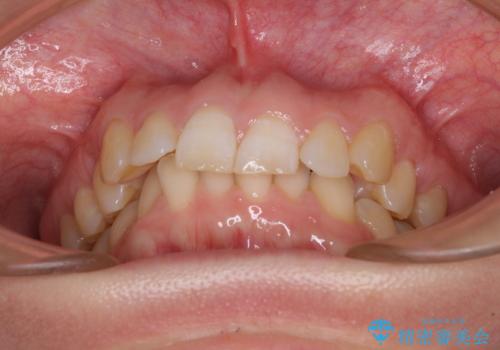

- 上顎前歯の前方に傾斜した咬み合わせを気にして来院された患者様です。

奥歯の咬み合わせを見ると、上顎が下顎に対して相対的に前方にありました。

深い咬み合わせを改善するためには、上顎臼歯を後方に移動させつつ、下顎の小臼歯を直立させる必要があります。